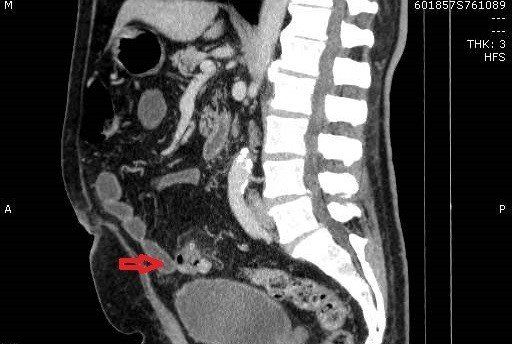

TC de abdome com contraste endovenoso fase excretora, evidenciando sinais de diverticulite aguda caracterizados por espessamento parietal do colon sigmoide, divertículos, densificação da gordura regional e presença de pequeno gás extraluminal, indicando pneumoperitônio discreto. Não há evidência de coleções pericolonicas associadas.

Na imagem, a diverticulite não complicada é caracterizada por filamento de gordura focal adjacente a um divertículo do cólon, geralmente o sigmóide. Uma pequena quantidade de líquido extraluminal e lóculos de gás podem estar presentes.

Encordoamento pericólico, muitas vezes desproporcionalmente proeminente em comparação com a quantidade de espessamento da parede intestinal

Espessamento segmentar da parede intestinal

Realce da parede do cólon

Perfuração diverticular

Extravasamento de gás e fluido para a pelve e cavidade peritoneal